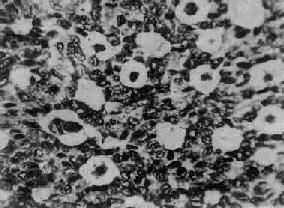

图13-20 粒层细胞瘤

瘤细胞排列成小卵泡型,部分细胞核呈现核沟

肉眼观,肿瘤呈圆形、卵圆形或分叶状,大小不等,多数小于15cm,表面光滑,常有完整的包膜。切面多为实性,质地稍硬,肿瘤呈黄白色,有些可呈囊性变,常有坏死出血区。多为单侧性。镜下,瘤细胞多呈小圆形或多角形,胞浆少。核圆、椭圆或梭形,核膜清楚,核内常可见纵沟,核染色质细,可见1~2个核仁,核分裂像较少见。组织学类型有以下几种:分化较好的瘤细胞常排列成小卵泡型(图13-20),呈菊形团或小腺泡状,中央为粉染蛋白液或退化的细胞核,称Call-Exner小体;有的排列呈大卵泡型、梁柱型或岛状等;分化较差的瘤细胞常排列呈弥漫型或波纹状、脑回状或肉瘤样构型。